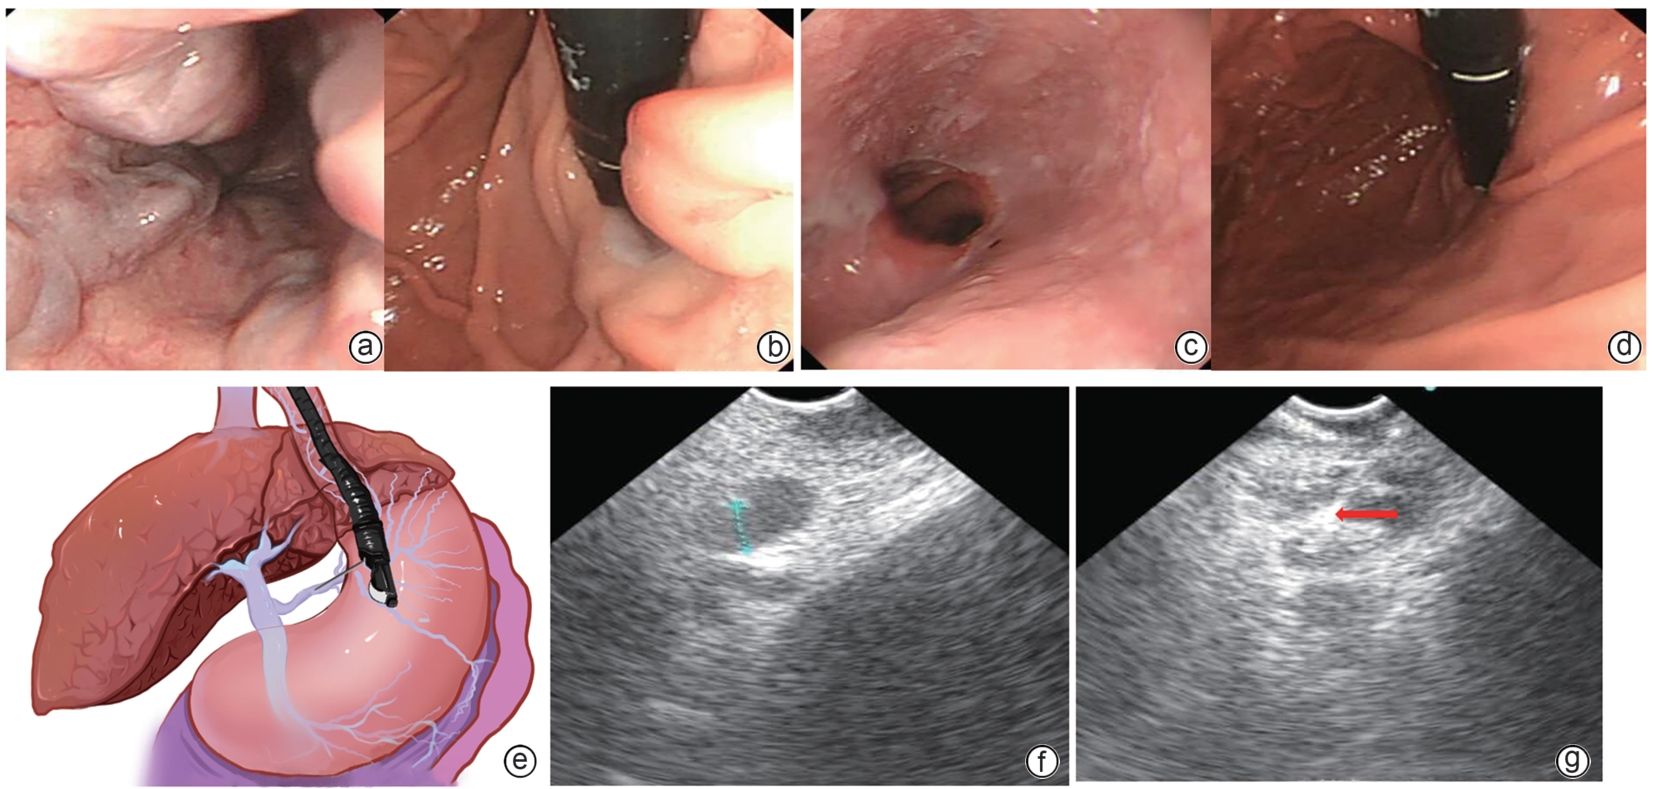

Safety and efficacy of puncture cyanoacrylate selective seal under endoscopic ultrasound versus traditional endoscopy in treatment of gastroesophageal varices: A randomized controlled trial

Jiali MA, Lingling HE, Hongshan WEI, Ping LI, Xiuxia LIANG

2025, 41(6): 1113-1119. DOI: 10.12449/JCH250617

Abstract(1029) HTML (179) PDF (1855KB)(58)

Abstract:

Objective  To investigate the safety and efficacy of puncture cyanoacrylate selective seal (PCSS) under endoscopic ultrasound in the treatment of gastroesophageal varices (GOV).  Methods  A total of 100 patients with liver cirrhosis who underwent endoscopic therapy for the secondary prevention of GOV bleeding in Beijing Ditan Hospital, Capital Medical University, from March 1 to December 31, 2023 were enrolled and randomly divided into PCSS group and traditional endoscopy group. The patients were followed up for 6 months after surgery, and the two groups were compared in terms of clinical outcome and complications. The primary outcome measure was the rate of alleviation or disappearance of GOV, and the secondary outcome measure was variceal rebleeding and death. The independent-samples t test was used for comparison of normally distributed or approximately normally distributed quantitative data between two groups, and the Wilcoxon non-parametric test was used for comparison of non-normally distributed quantitative data between two groups; the chi-square test or the Fisher’s exact test was used for comparison of qualitative data between two groups.  Results  There were 50 patients in the PCSS group, among whom 1 patient was lost to follow-up, and there were 50 patients in the traditional endoscopy group, among whom 3 patients were lost to follow-up. There were no significant differences between the two groups in baseline data such as age, sex, Child-Pugh class, varices grade, and GOV typing (all P>0.05). Compared with the traditional endoscopy group, the PCSS group had significantly better results of the number of endoscopic treatment sessions (t=-15.671, P=0.001), the total amount of tissue adhesive used (t=-2.830, P=0.006), and the rate of alleviation or eradication of varices sclerosis (χ2=7.078, P=0.029). Both groups had low rates of postoperative rebleeding, adverse reactions, and complications, and there were no significant differences between the two groups (all P>0.05).  Conclusion  Compared with traditional endoscopy, PCSS can significantly enhance treatment outcome while maintaining safety standards.